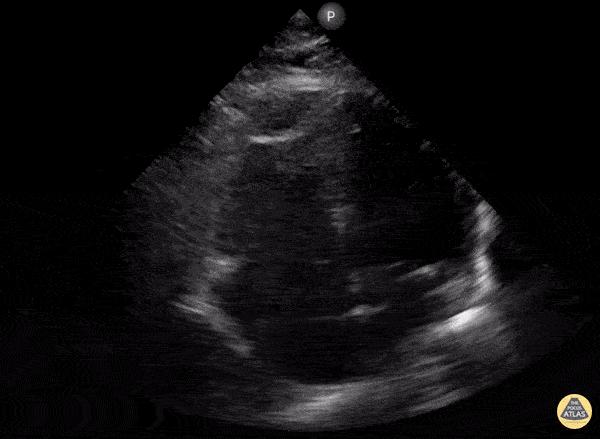

Right Ventricular Dysfunction - McConnell's Sign Due to NSTEMI

An elderly patient presented with shortness of breath and generalized weakness found to have an NSTEMI and high degree AV block. Bedside focused cardiac ultrasound with 4 chamber apical view revealed: McConnell’s Sign. Chest CTA neg for PE. Patient underwent cardiac catherization with culprit lesion being mid RCA. Not all McConnell’s sign is related to acute PE. In this case RV infarct secondary to NSTEMI with mid RCA occlusion s/p DES PCI with complete resolution of AV block. Dat Lu MD, Internal Medicine Clerkship Site Director Kaiser Roseville